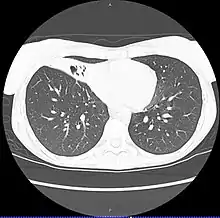

CT scan of patient with right middle lobe aspiration and Mycobacterium avium infection consistent with Lady Windermere syndrome

MAC usually affects patients with abnormal lungs or bronchi. However, Jerome Reich and Richard Johnson describe a series of six patients with MAC infection of the right middle lobe or lingula who did not have any predisposing lung disorders.[17][18]

The right middle lobe and lingula of the lungs are served by bronchi that are oriented downward when a person is in the upright position. As a result, these areas of the lung may be more dependent upon vigorous voluntary expectoration (cough) for clearance of bacteria and secretions.

Since the six patients in their retrospective case series were older females, Reich and Johnson proposed that patients without a vigorous cough may develop right middle lobe or left lingular infection with MAC. They proposed this syndrome be named Lady Windermere syndrome, after the character Lady Windermere in Oscar Wilde's play Lady Windermere's Fan. However, little research has confirmed this speculative cause.[19]